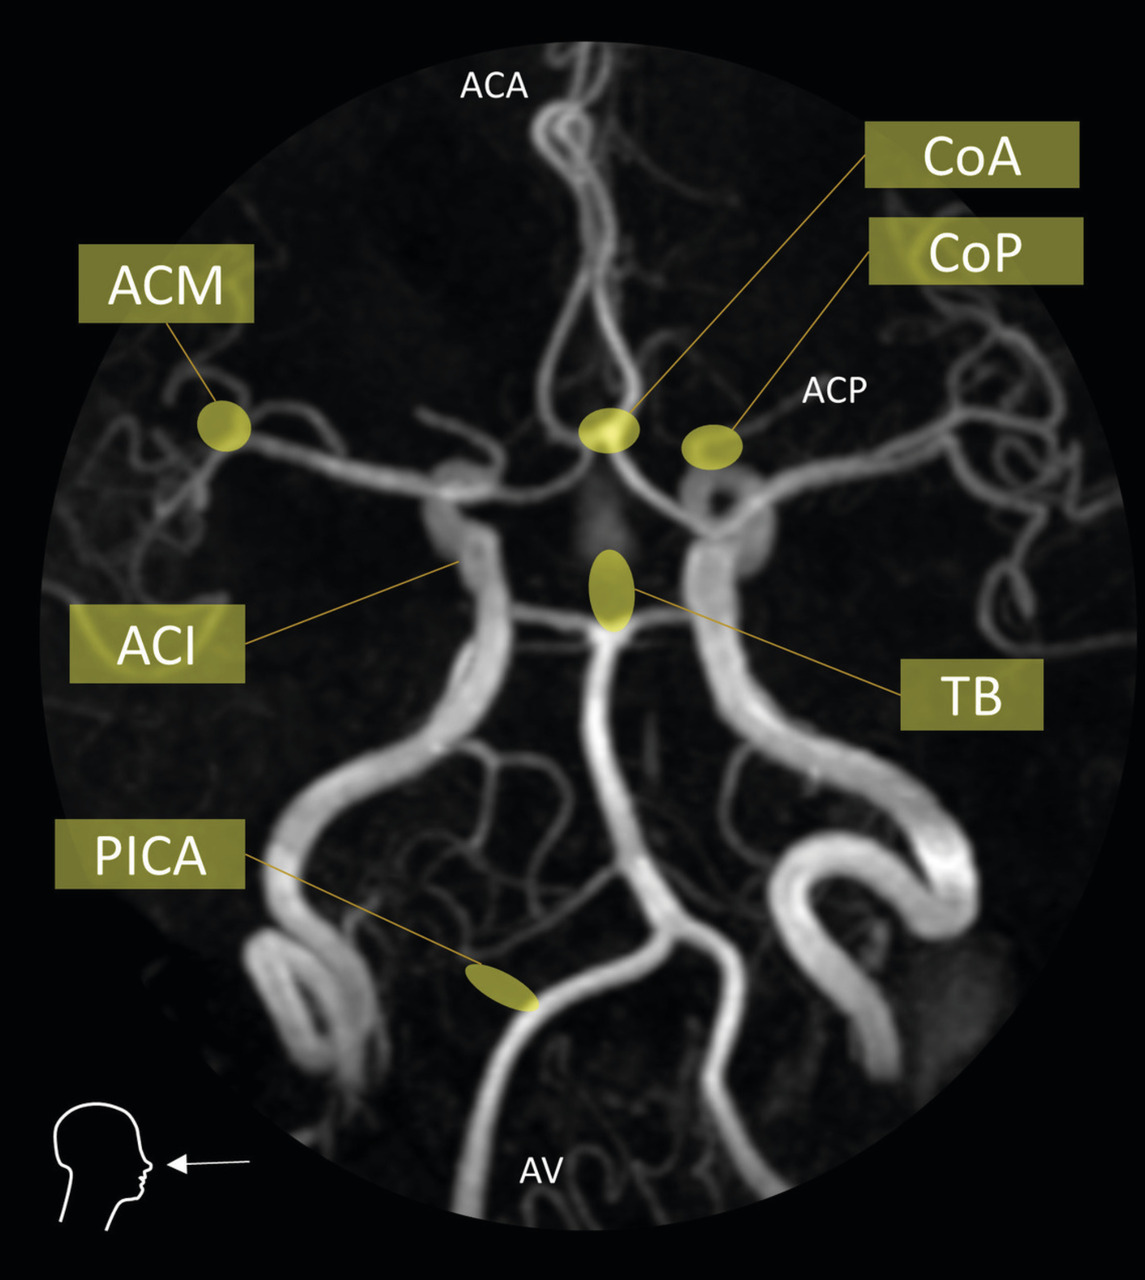

Il est capital de réaliser une imagerie artérielle dès la phase diagnostique pour planifier la suite de la prise en charge. Dans cette indication, l’angio­scanner a une meilleure sensibilité que l’angio-IRM en temps de vol pour la détection des anévrismes de taille inférieure à 3 mm. Une attention particulière est portée aux sites de développement préférentiel des anévrismes dits « de bifurcation ». (fig. 3).